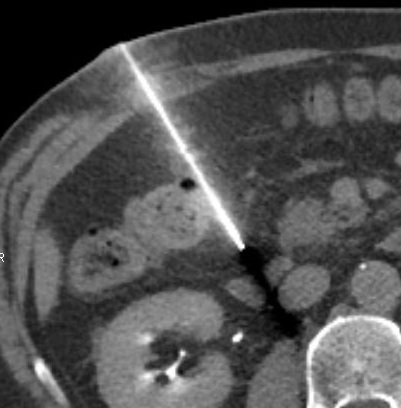

Dans sa pratique, le radiologue exposait ses mains dans le faisceau primaire de rayonnements lors du guidage de l’aiguille par radioscopie, lors de petits examens interventionnels. Cet événement nous rappelle que tous les actes de radiologie interventionnelle, même les plus anodins, doivent faire l'objet d'une attention accrue lorsqu'il s'agit de l'exposition des travailleurs aux rayonnements ionisants. Cet événement a été classé au niveau 1 de l'échelle INES.